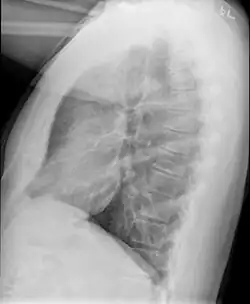

Example of early disease with mild flattening of the diaphragm

Bronchiolitis obliterans is often diagnosed based on the symptoms of obstructive lung disease following lung injury. The definitive diagnosis is through biopsy, but due to the variable distribution of lesions, leading to falsely negative tests, and invasive nature of this procedure it is often not performed.[6][11] Several tests are often needed to diagnose bronchiolitis obliterans, including spirometry, diffusing capacity of the lung tests (DLCO), lung volume tests, chest X-rays, high-resolution CT (HRCT), and lung biopsy.[11][4]

Medical imaging

Early in the disease chest radiography is typically normal but may show hyperinflation.[6] As the disease progresses a reticular pattern with thickening of airway walls may be present.[4][6] HRCT can also show air trapping when the person being scanned breathes out completely; it can also show thickening in the airway and haziness in the lungs.[11] A common finding on HRCT is patchy areas of decreased lung density, signifying reduced vascular caliber and air trapping. This pattern is often described as a "mosaic pattern", and may indicate bronchiolitis obliterans.[6]